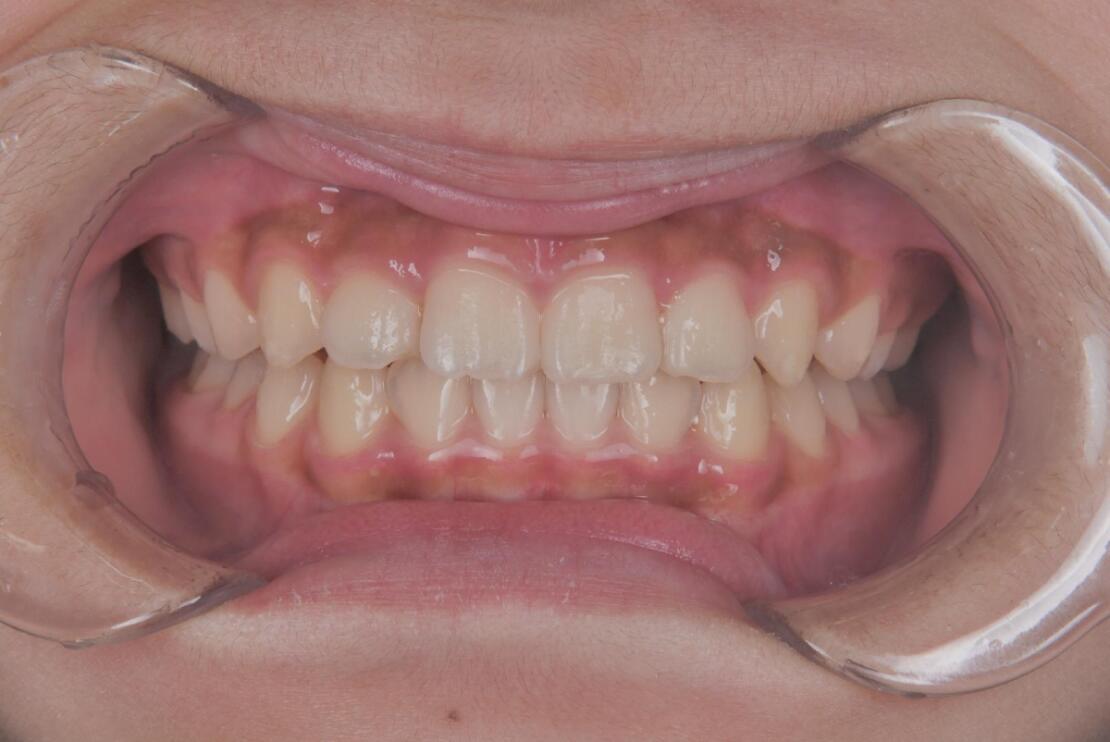

AFTER

治療期間は合計2年9ヶ月で、上下前歯のガタつきは改善し、見た目と機能の両面が整った歯列へと改善しました。